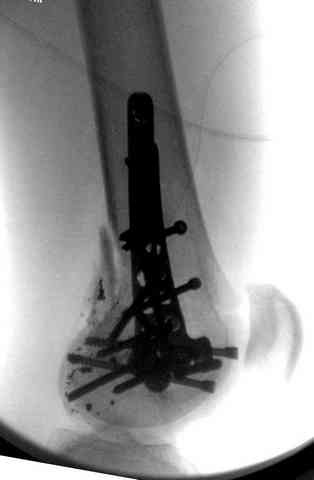

Здесь представлены несколько случаев лечения огнестрельного перелома

1 Проксимальный перелом бедра, антеградный гвоздь

2 внутрисуставной перелом дистального бедра с удалением пули

3 сегментарный перелом бедра с переломом Хоффа фрагментом, сделано из минимального доступа